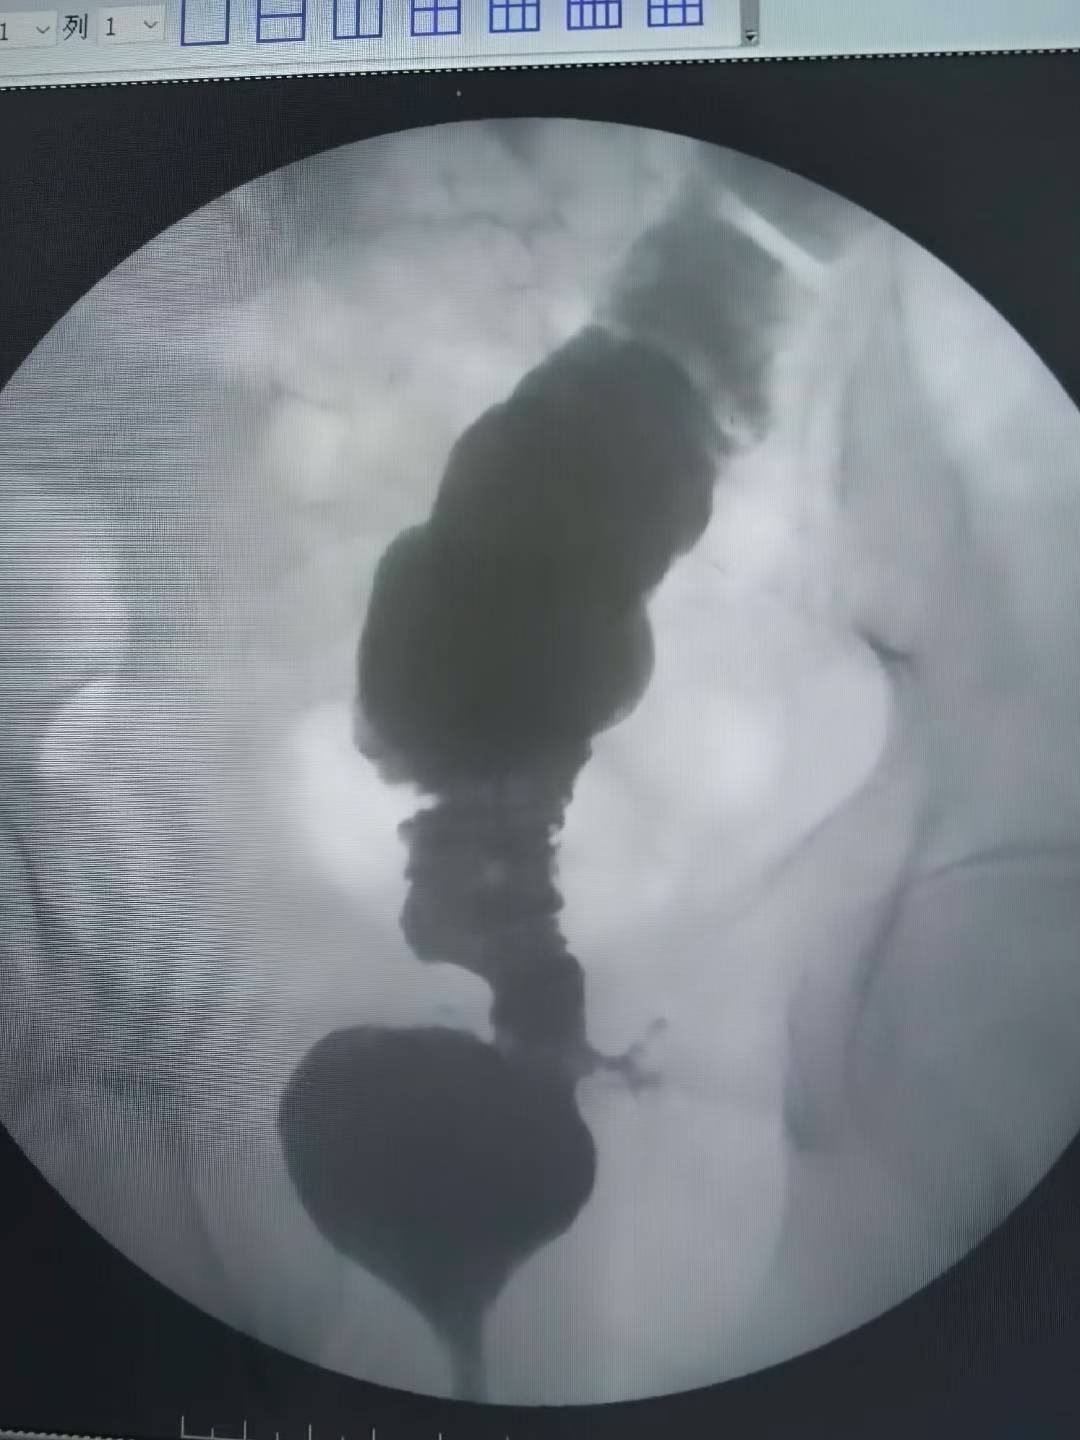

上午一台食管癌术后吻合口狭窄球囊扩张成型 上午一台食管癌术后吻合口狭窄...